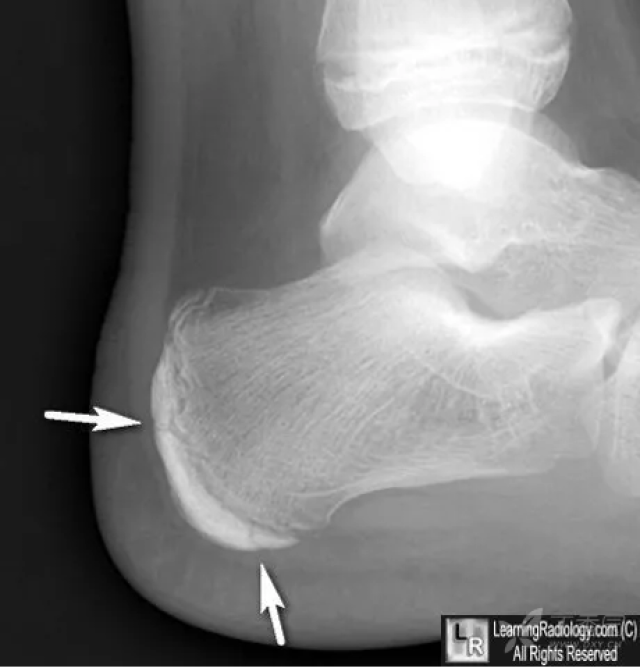

跟骨骨骺

请注意:儿童跟骨骨骺不同与其他部位的骨骺,密度均匀,致密(绿箭

跟骨后缘多个骨化中心骨骺所致

骨囊肿,脂肪瘤,骨巨细胞瘤 跟骨结节骨骺出现年龄:一般男性为7—11岁

跟骨骨骺约在12~14岁时闭合,主要发病原因也是大量运动导致跟腱点与